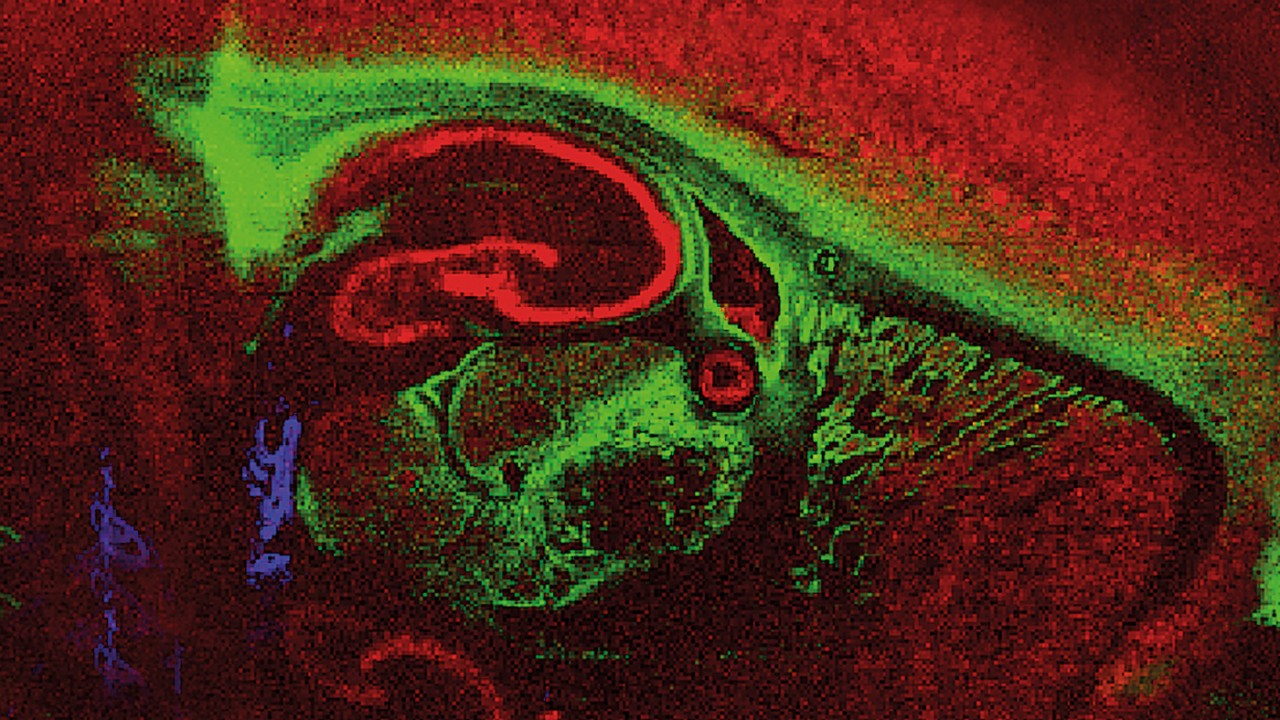

Comparative analysis of multiple samples can be visualized in both 2D and 3D, enabling a multitude of applications in pharmaceutical drug development, tissue-resolved biomarker discovery, and translational pathology research to complement immunohistochemistry.

Label-free MALDI Imaging for all classes of molecules – from proteins to small molecules

SCiLS™ Lab can be used for the processing and analysis of multiple MALDI Imaging datasets, allowing them to be loaded and arranged side by side. Compositions of data sets of virtually unlimited size can be visualized and statistically analyzed for detailed interpretation. SCiLS™ Lab can be used to generate and visualize 3D models from consecutive 2D MALDI Imaging datasets. Moreover, the SCiLS™ Ion Image Mapper can be used to fuse spatial multiomics data sets which can be jointly analyzed in SCiLS™ Lab, providing unparalleled actionable knowledge.

Fusion and analysis of MALDI Imaging spatial multiomics datasets obtained from a single tissue section made possible by SCiLS™ Lab.